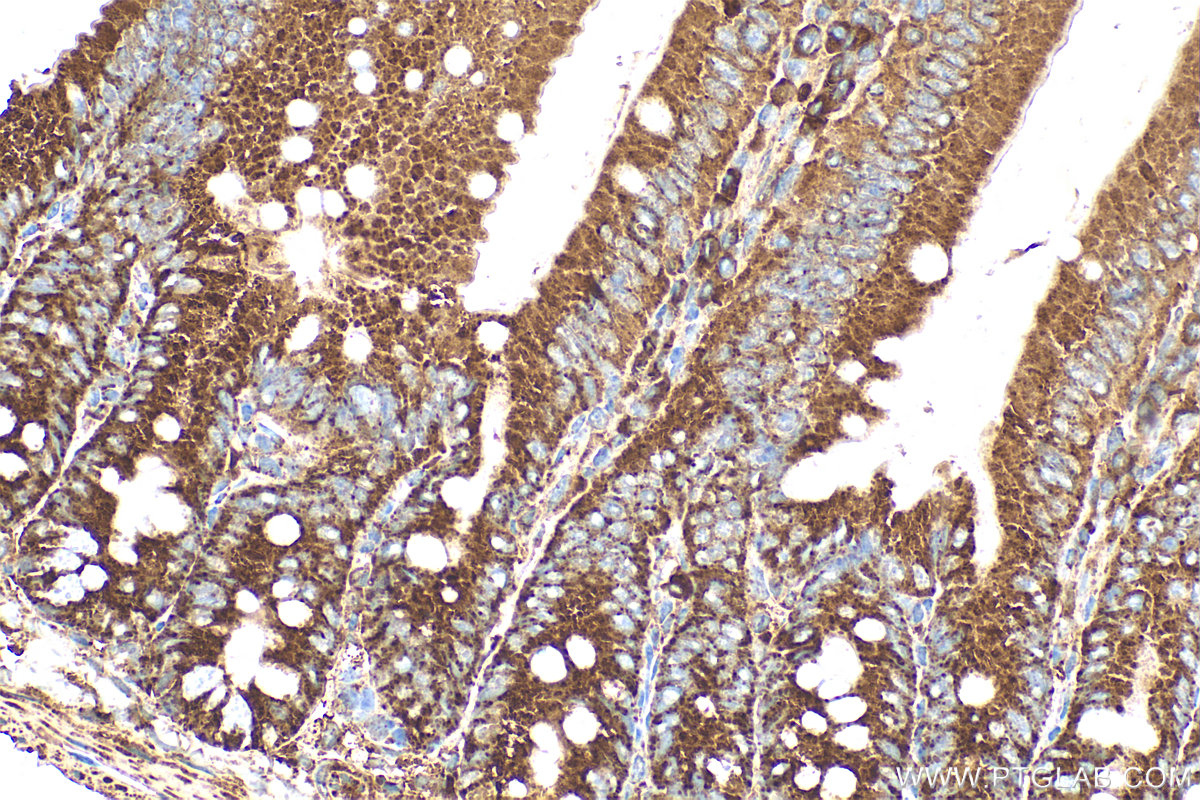

| Positive IHC detected in | mouse small intestine tissue, human brain tissue, human small intestine tissue Note: suggested antigen retrieval with TE buffer pH 9.0; (*) Alternatively, antigen retrieval may be performed with citrate buffer pH 6.0 |

| Immunohistochemistry (IHC) | IHC : 1:50-1:500 |